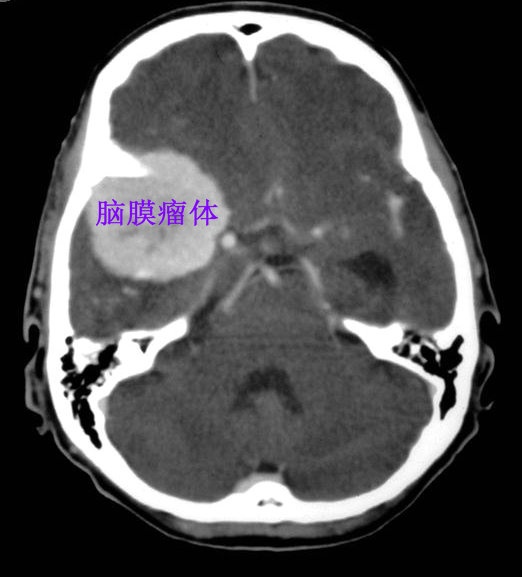

图 CT检查可见右侧脑底部的脑膜瘤